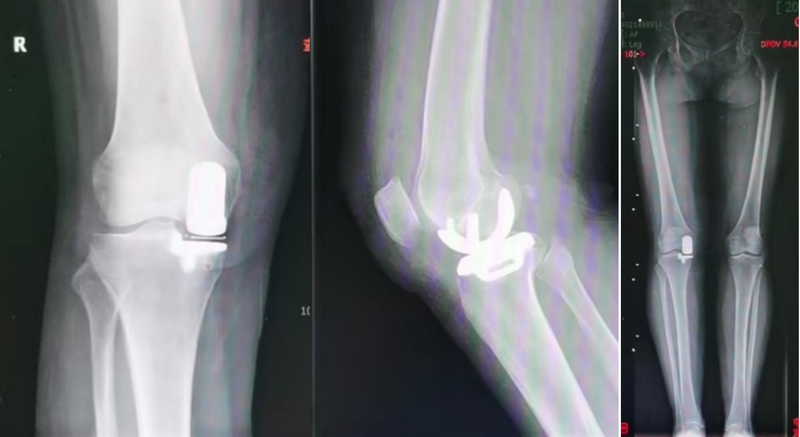

什么是膝關(guān)節(jié)單髁置換術(shù)

一、什么是單髁置換人們的膝關(guān)節(jié)分為三大部分,包括內(nèi)側(cè)間室、外側(cè)間室、髕股間室。雖然膝關(guān)節(jié)疾病會(huì)累及任意一個(gè)間室或者全部累及,但是其實(shí)很多骨性關(guān)節(jié)炎患者累及范圍以內(nèi)側(cè)間室為主。對(duì)于這部分患者,其實(shí)僅需要進(jìn)行內(nèi)側(cè)間室的置換手術(shù),就可以獲得滿意的臨床效果,也就是膝關(guān)節(jié)單髁置換術(shù)。二、單髁置換適應(yīng)癥i.膝關(guān)節(jié)退變以內(nèi)側(cè)間室為主,可以合并髕股關(guān)節(jié)退變、前交叉韌帶損傷。ii.非炎性關(guān)節(jié)炎,比如骨性關(guān)節(jié)炎、創(chuàng)傷性關(guān)節(jié)炎。例如類風(fēng)濕性關(guān)節(jié)炎、銀屑病性關(guān)節(jié)炎、痛風(fēng)性關(guān)節(jié)炎等是不適合做單髁置換的,因?yàn)檫@些疾病導(dǎo)致的關(guān)節(jié)炎,往往是累及三間室。iii.一般來說,膝內(nèi)翻<15°,屈曲攣縮小于15°。三、單髁置換優(yōu)勢(shì)膝關(guān)節(jié)單髁置換術(shù)實(shí)現(xiàn)了中晚期膝關(guān)節(jié)疾病的微創(chuàng)化治療。和全膝置換術(shù)相比,單髁置換僅僅對(duì)已經(jīng)磨損的內(nèi)側(cè)間室軟骨、半月板進(jìn)行手術(shù)操作、替代,也就是“原拆原建”,不破壞膝關(guān)節(jié)髕股關(guān)節(jié)、外側(cè)間室,保留膝關(guān)節(jié)本身的全部韌帶。手術(shù)創(chuàng)傷小、感染率低、住院時(shí)間短、安全性高是單髁置換術(shù)的優(yōu)點(diǎn)。單髁置換術(shù)后康復(fù)更快,術(shù)后第二天就可以開始自行站立行走,很多不需要助行器的輔助。四、總結(jié):?jiǎn)西林脫Q術(shù)是個(gè)微創(chuàng)關(guān)節(jié)置換手術(shù),適合很多人,但并不適合所有人。醫(yī)生需要結(jié)合患者癥狀、體征、影像改變,還有患者基礎(chǔ)身體條件、年齡、訴求進(jìn)行綜合評(píng)估。對(duì)于適合的患者,單髁置換是膝關(guān)節(jié)病患者的福音。